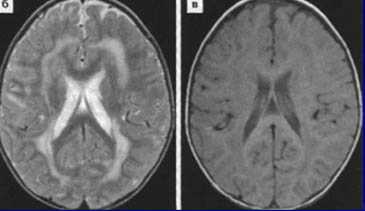

Диагностические мероприятия имеют комплексный характер и позволяют отдифференцировать метахроматическую лейкодистрофию от других нейродегенеративных заболеваний и других форм лейкодистрофии. Проводится люмбальная пункция, при исследовании цереброспинальной жидкости определяется повышенная концентрация белка, дефицит арилсульфатазы, белково-клеточная диссоциация. Электромиография выявляет увеличение длительности проведения нервных импульсов. КТ головного мозга визуализирует расширенные желудочки и определяет пониженную плотность белого церебрального вещества. МРТ головного мозга выявляет очаги демиелинизации.

С целью диагностики вида метаболической аномалии проводится целый ряд биохимических тестов с определением уровня ферментов и накапливающихся метаболитов. Очаги демиелинизации хорошо визуализируются при помощи МРТ, могут быть обнаружены и на КТ головного мозга. Обычно демиелинизация видна на МРТ головного мозга еще до клинической манифестации лейкодистрофии. Благодаря развитию генетики, лейкодистрофия имеет разработанную ДНК-диагностику, а отдельные ее формы (метахроматическая, адренолейкодистрофия, глобоидно-клеточная) — возможность пренатального диагностирования.

Томограммы метахроматической лейкодистрофии

МРТ головного мозга необычайно высоко чувствительна к дисмиелогенным нарушениям, но не очень специфична в плане дифференциальной диагностики внутри группы. При всех этих патологиях на Т2-взвешенных МРТ и МРТ, отражающих протонную плотность, видны гиперинтенсивные поля в белом веществе.